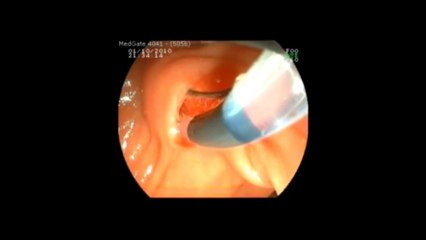

Prof Dr Kayıhan Günay polip çıkarılması.